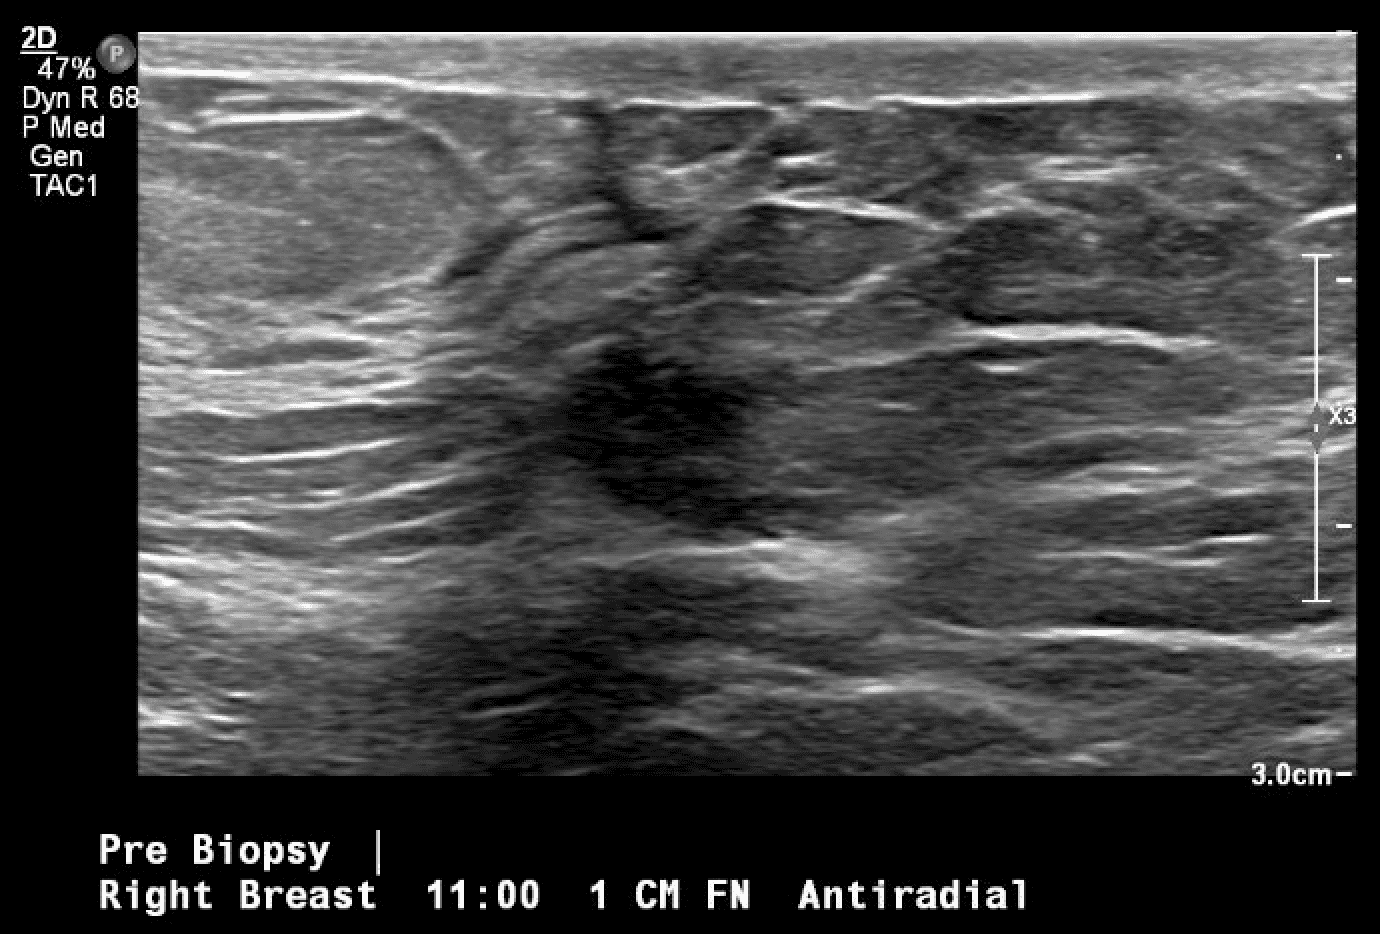

Patient is a 46-year-old premenopausal female with no other contributing past medical or surgical history who presented initially to the breast surgery clinic after her annual screening mammogram discovered a nonpalpable right breast mass measuring 0.6 x 0.8 x 0.7 cm at 11 o’clock (oc), 1 cm from the nipple (FTN) (Figure 1). She had three previous screening mammograms without any notable findings. The screening mammogram was declared inconclusive (BI-RADS 0), and a breast ultrasound was completed with similar findings. Further discussion with the patient revealed that there had been some bloody discharge seen in the right side of her bra over the last few months, but no other concerns or symptoms. Given the inconclusive imaging findings, it was decided to perform a diagnostic mammogram for a more specific assessment (Figures 2a and 2b) following an ultrasound-guided core-needle biopsy and localizing clip placement for a tissue diagnosis (Figure 3). Pathology revealed an intraductal papilloma with ductal hyperplasia and apocrine metaplasia without atypia. Given her continued bloody nipple discharge, there was concern for possible underlying premalignant cells (discussed more later); thus, it was recommended that the patient undergo partial mastectomy. The mass remained nonpalpable; therefore, a Savi Scout would be placed just before operative intervention to help localize the area of concern.

Figure 3. Ultrasound-guided localization and biopsy of the breast mass in question, first seen on screening mammogram. Post-biopsy image includes typical tissue changes seen once a core-needle biopsy is performed (hash mark).